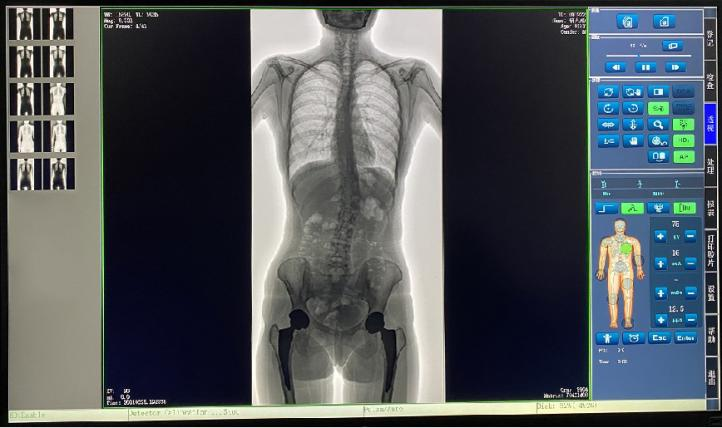

數(shù)字動(dòng)態(tài)DR 新品PLX8600大視野動(dòng)態(tài)平板DR產(chǎn)品說(shuō)明:

? ? 普愛(ài)醫(yī)療新推出一款動(dòng)態(tài)平板DR-PLX8600,這款產(chǎn)品可攝影、可透視、可造影,臨床適用范圍廣泛,可滿足不同臨床拍攝需求。一體式的機(jī)架,擺位簡(jiǎn)單快捷,不僅融合了市面上17英寸動(dòng)態(tài)DR的所有功能,還有獨(dú)具特色的超大動(dòng)態(tài)視野范圍,給臨床應(yīng)用帶來(lái)醫(yī)療診斷價(jià)值,降低醫(yī)院設(shè)備投入成本,獲得更大收益。

? ? 1.專為大視野臨床應(yīng)用打造的平板動(dòng)態(tài)DR,圖像不拼接,有效簡(jiǎn)化影像科室檢查流程,提高診斷精度,降低患者吸收的輻射劑量。

? ? 2.解決了拼接圖像存在密度不均勻,拼接處圖像配準(zhǔn)和放大效應(yīng)等問(wèn)題,輻射劑量小。

? ? 7.自研軟件系統(tǒng),功能區(qū)劃分合理,操作便捷,圖像處理清晰。